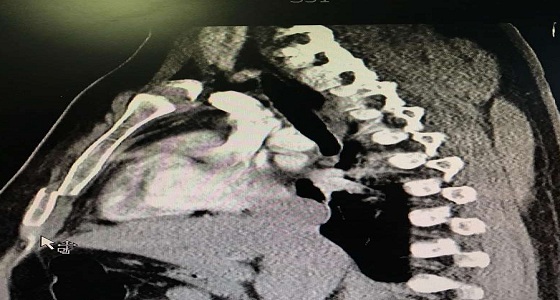

نجاح عملية تثبيت كسر بالفقرة القطنية الأولى في مجمع الدمام الطبي